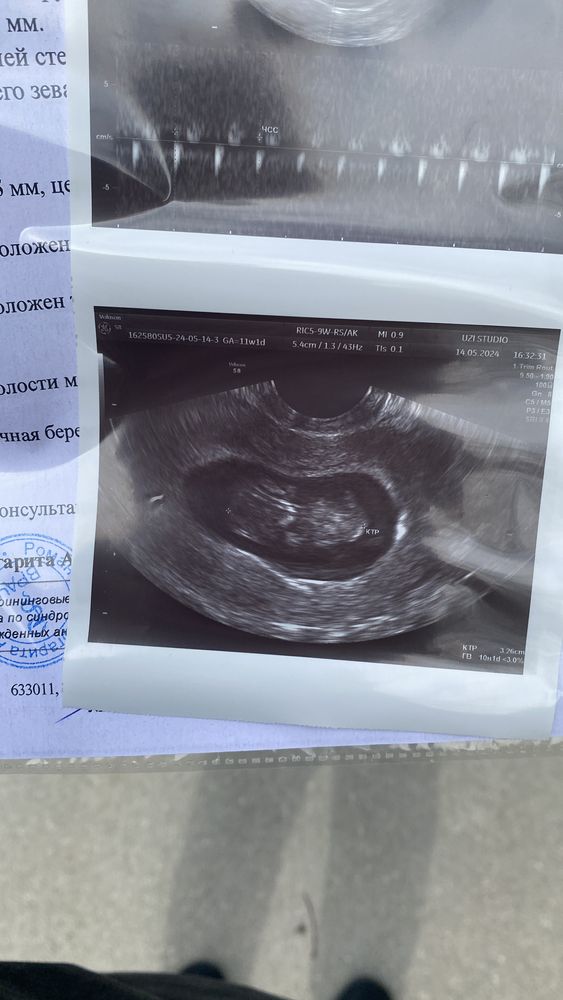

Так выросли за 4 недели , мне совсем не вериться, я уже услышала твое сердечко , и этой рай для ушей😀😘